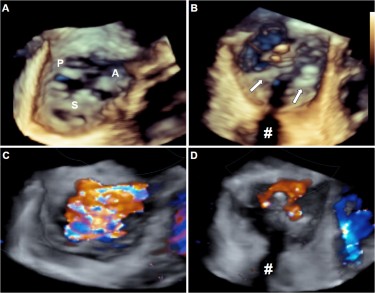

Severe tricuspid regurgitation was seen in 25 of the patients who presented signs of an acute right heart dysfunction. Der mittlere Gradient über der Aortenklappe betrug 82 48 mmHg die Ejektionsfraktion lag bei 503 71. Bei der Trikuspidalinsuffizienz handelt es sich um eine Schlussunfähigkeit der Trikuspidalklappe mit konsekutiver Regurgitation von Blut aus dem rechten Ventrikel in das rechte Atrium während der Systole Abb.